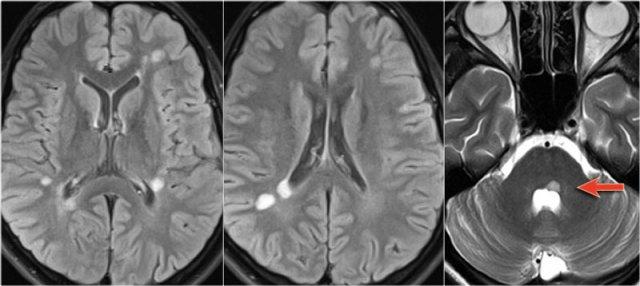

MS: tổn thương khu trú đoạn ngắn hình nêm ở cột sau tủy sống kèm theo các tổn thương chất trắng quanh não thất điển hình.

MRI não cho thấy các tổn thương quanh não thất và một tổn thương ở thể chai.

Các vị trí này rất đặc trưng cho MS.

Ở một bệnh nhân khác có các tổn thương không đặc hiệu trong tủy sống.

Chỉ dựa vào khảo sát cột sống đơn thuần, chúng ta có một chẩn đoán phân biệt rộng.

Tuy nhiên khi khảo sát thêm não, sẽ rõ ràng rằng chúng ta đang đối mặt với MS.

Tiếp tục xem các hình ảnh của não.

Trong trường hợp này, các hình ảnh trên não rất hữu ích.

Vị trí của các tổn thương rất điển hình: cầu não, quanh não thất và dưới vỏ não.